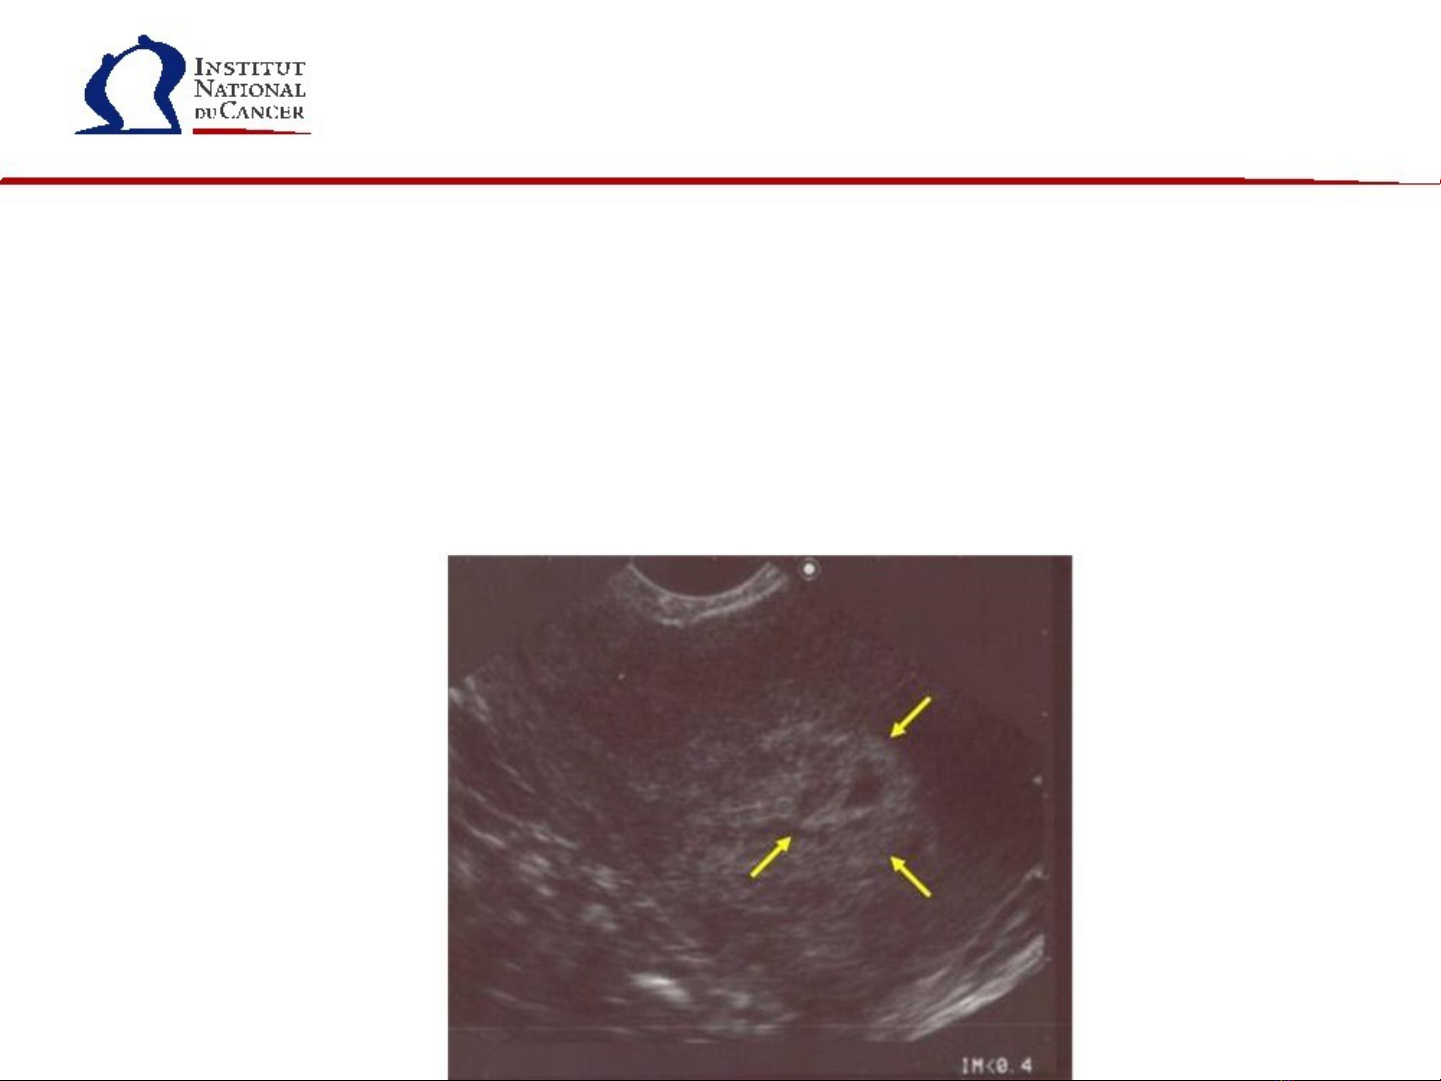

Siêu âm vùng ch u, đ ng b ng trên x ng mu và ngã âm đ o ậ ườ ụ ươ ạ

đ tìm d u hi u quá s n n i m c t cungể ấ ệ ả ộ ạ ử